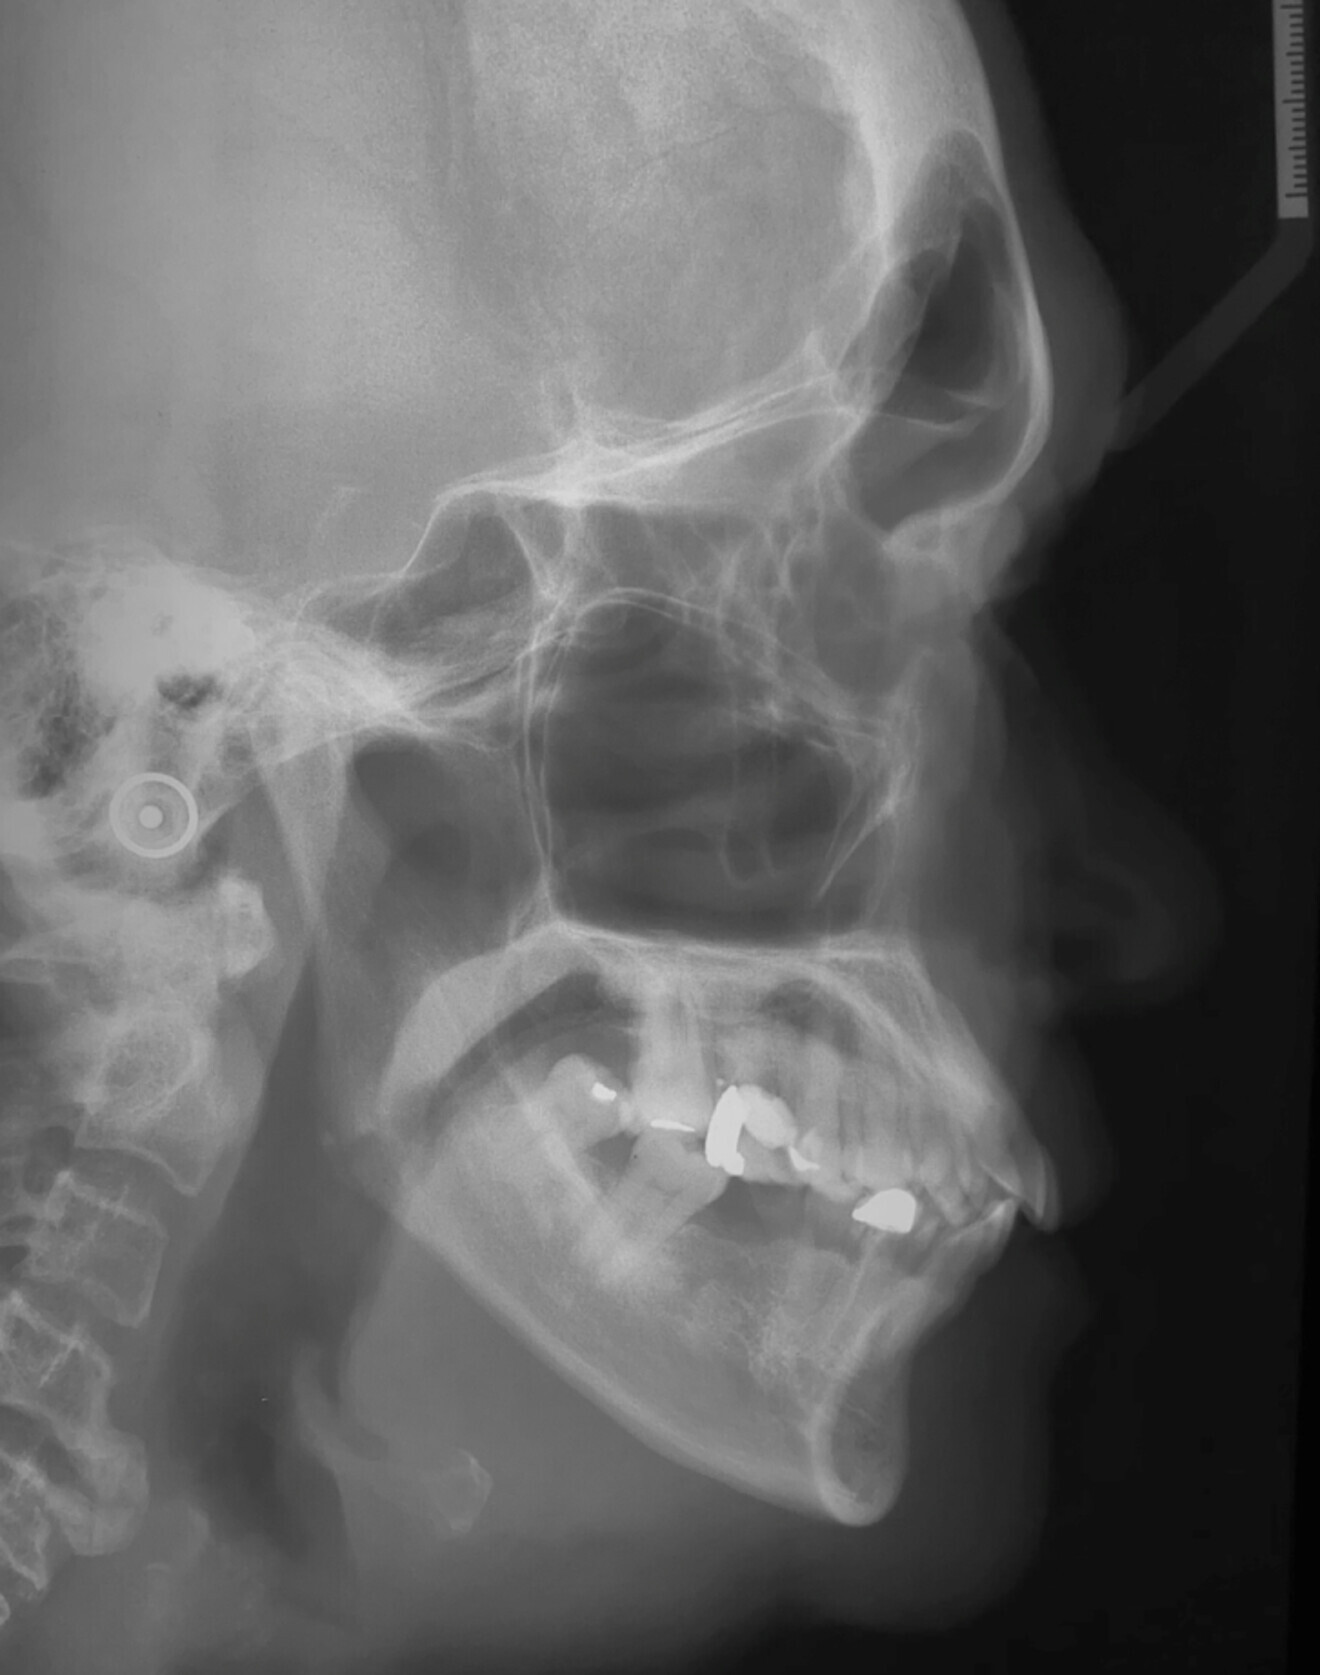

Cephalometric analysis:

Go Me Sn: 39

Saddle: 119

Articular: 140

Gonial: 140

Inner: 399

ANSMe/Nme: %

Jarabak Ratio (Sgo/Nme): 59 %

Max height: 50

FMA: 29

High vertical growth pattern

SNA: 90

SNB: 95

ANB: -5

Wits: -2mm

McNamara: 2mm

Corpus ratio : 55/59

Max Depth: 100

Holdaway: 6/1

Class II skeletal pattern due to prognathic maxilla and small mandible.

Poor pogonion projection

11

ISN: 128

IMPA: 100

I – I : 93

UI – OP :38

LI – OP : 40

OP – SN : 15

OP – FH : 6

UI – PP : 132

Increased upper and lower incisors.

Flat occlusal plane.